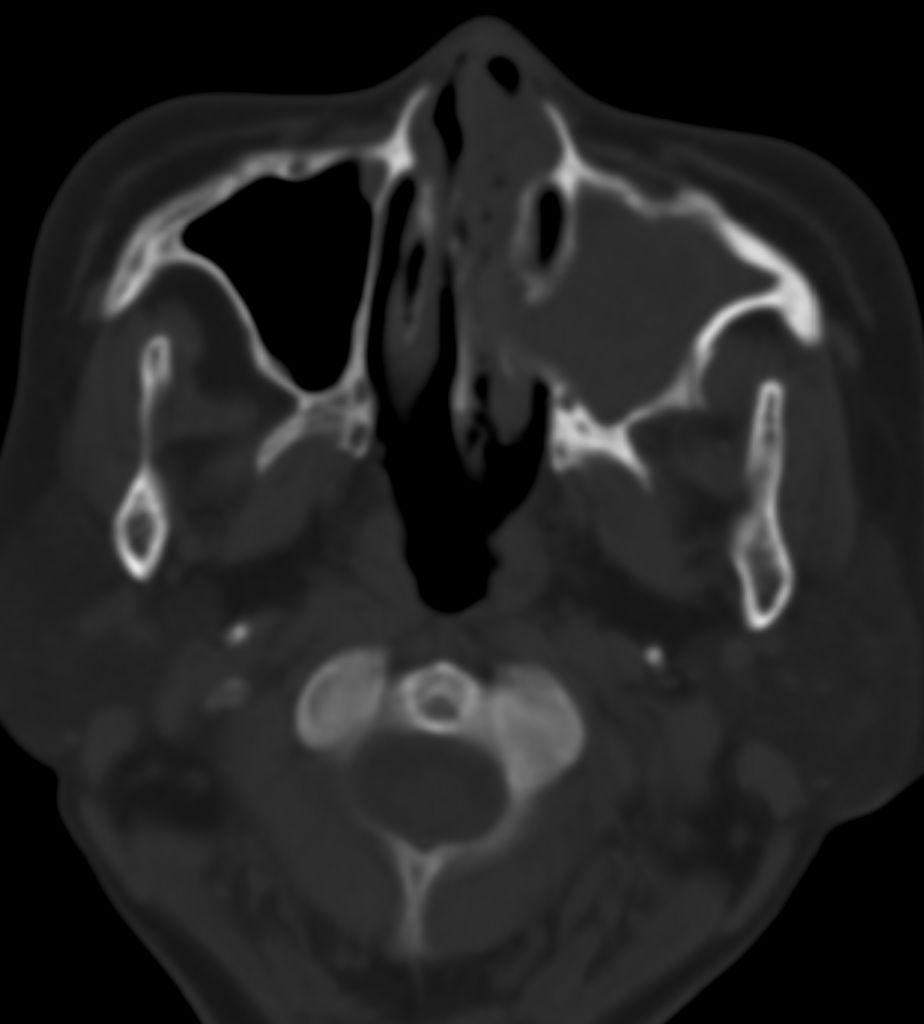

女,69岁。鼻出血2月多。(会诊病史就这样简单)鼻副窦ct检查如下:

左侧鼻腔及上颌窦见软组织块影,左侧上颌窦腔扩大,骨质吸收,右侧上颌窦见半圆形软组织密度影,鼻中隔向右侧弯曲,左侧鼻和鼻窦内翻型乳头状瘤可能性大,建议增强。

左侧上颌窦及鼻腔内见软组织密度影,其内密度不均匀,见斑片状高密度影,右侧上颌窦腔明显扩大,窦壁吸收变薄,鼻中隔右偏,右侧上颌窦见一半圆形软组织密度影,边界清楚,其内密度均匀。诊断,1、左侧鼻腔及上颌窦内翻乳头状瘤可能性大,上颌窦癌,息肉及霉菌性上颌窦炎待除外。2、右侧上颌窦粘膜下囊肿。

1)考虑左侧上颌窦内翻乳突状瘤突入左侧鼻腔。2)副鼻窦炎,右侧上颌窦黏膜下囊肿。

病理:霉菌性左侧上颌窦炎伴左侧上颌窦纤维组织增生。

窦腔密度不均匀增高,无明显钙化征象,后外侧及内侧窦壁膨胀明显,局部破坏消失,筛窦受累及,但双侧对比发现左侧窦壁骨质有硬化增白现象,这可能是支持左侧霉菌性上颌窦炎的主要依据点。